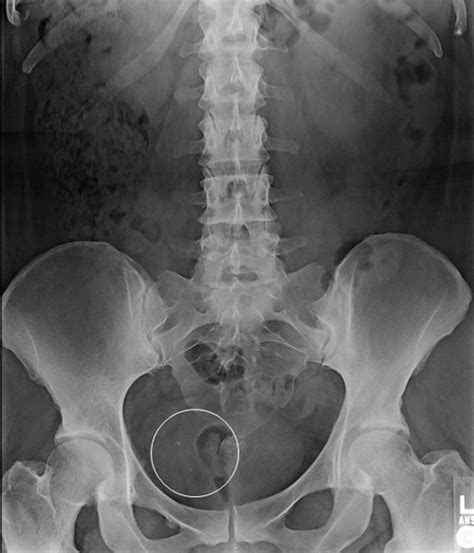

Phleboliths are small, calcified deposits that form within veins. They are typically composed of calcium and other minerals and can vary in size from a few millimeters to several centimeters. These deposits are often incidental findings during imaging studies, such as X-rays, CT scans, or MRIs. While phleboliths can occur in various parts of the body, their presence in the pelvis is particularly noteworthy due to the anatomical complexity of the region.

Detecting phleboliths in the pelvis typically involves imaging techniques that can visualize the calcified deposits. The most common diagnostic methods include:

• X-Rays: Plain radiographs can sometimes detect phleboliths, especially if they are large enough. However, X-rays are less sensitive compared to other imaging modalities.

• Incidental Findings: Many phleboliths are discovered incidentally during imaging studies performed for other reasons. In such cases, they are often benign and do not require any intervention.

Case Study 2: A 60-year-old man underwent a routine CT scan for abdominal pain. The scan incidentally detected a small phlebolith in the pelvic region. Since the phlebolith was asymptomatic and not associated with any underlying condition, no further treatment was required.